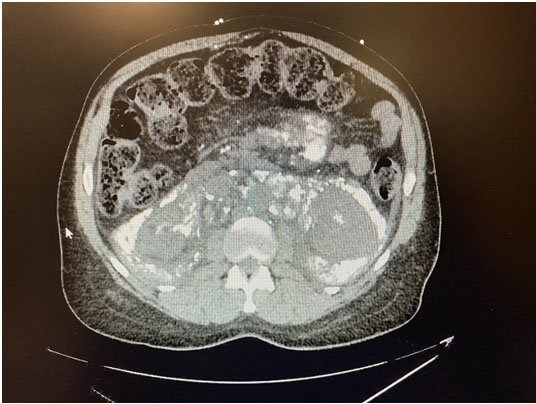

Anemia, cloudy yellow urine, leukocyturia, bacteriuria were found in laboratories, rest within normal values (Figure 3). At 48 hours the result of the bacteriological culture of the catheter tip was with E. coli sensitive only to ertapenem, for which hospital medical treatment was started and the patient was discharged after 48 hours to continue home management. Medical surveillance is continued by the outpatient clinic, reassessing the patient at 3 weeks with light yellow urinary output without stench (Figure 4).

Figure 3: Cloudy yellow urinary sample.